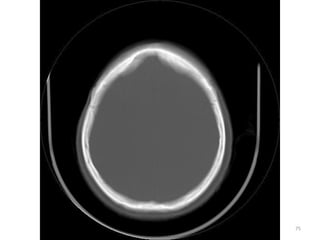

SUPRA TENTORIAL

IMAGENS ÓSSEAS